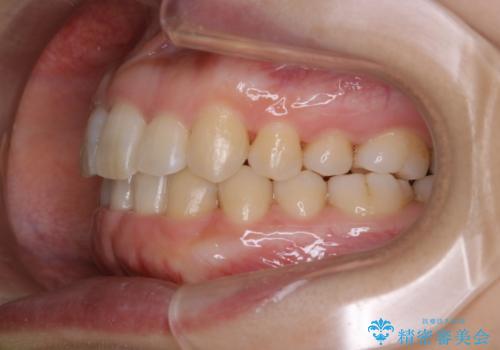

インビザライン・ライトでの抜歯矯正治療 (スリーインサイザー仕上げ)

- 上下の前歯のがたつきが気になるとのことで来院されました。最短治療とインビザラインでの矯正治療をご希望されました。

前歯のがたつきを無くすためには、スペースを確保する必要があります。上の前歯のがたつきは軽度ながたつきのため、歯と歯の間を研磨をして、そのスペースを使い並べていきます。下の前歯は、1本前歯を抜いて研磨せずに、その抜歯したスペースを使い並べることになりました。

インビザライン・ライトにて矯正治療を行うことになりました。

下の前歯は、スリーインサイザー仕上げと言って、通常前歯は4本ありますが(犬歯はいれていない)、そのどれか1本を抜歯して前歯を3本にして矯正治療を行うことを言います。また、先天的に歯の本数が少ない方もいますので、矯正治療を行っていなくても元々スリーインサイザーの方もいます。